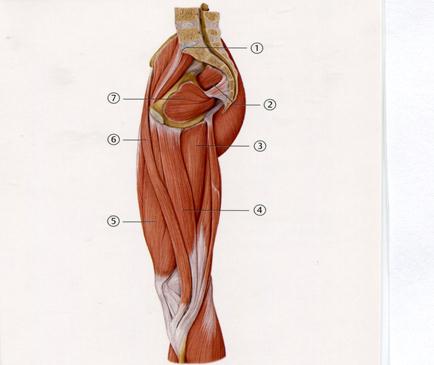

41. Төменде көрсетілген суреттегі белгіленген № 6 бұлшықетті атаңыз.

+А.Балтыр

В. Екі басты

С.Жартылай жарғақты

D. Жартылай сіңірлі

Е. Үлкен бөксе

69. Төменде көрсетілген суреттегі белгіленген № 2 бұлшықетті атаңыз.

A. Алмұрт тәрізді

+B. Нәзік

C. Тігінші

D. Төртбасты

E. Ішкі жапқыш

70. Төменде көрсетілген суреттегі белгіленген № 3 бұлшықетті атаңыз.

A. Арқаның аса жалпақ

B. Трапеция тәрізді бұлшықеттің жоғарлаған бөлімі

C. Трапеция тәрізді бұлшықеттің ортаңғы бөлімі

+D. Трапеция тәрізді бұлшықеттің төмендеген бөлімі

E. Үшбасты

93.Жарақат кезінде жрақаттанған адамның санының артқы топ бұлшық еттерінің қызметі бұзылды. Осы жағдайда тізе буынының қандай қызметі бұзылады?

A. Әкету

B. Әкелу

C. Бұру

D++. Бүгу

E. Жазу

94 Науқасқа сапасыз бұлшықетішілік инъекциядан кейін үлкен бөксе бұлшықеттінің абсцесі пайда болды. Жамбас буынының қандай қызметі шектеледі?

A++. Әкету

B. Әкелу

C. Бүгу

D. Сыртқа бұру

E. Ішке бұру